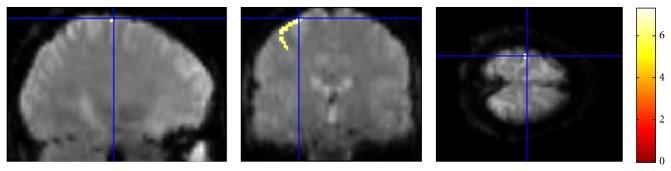

Modeling the blood oxygenation level dependent (BOLD) signal has been a subject of study for over a decade in the neuroimaging community. Inspired from fluid dynamics, the hemodynamic model provides a plausible yet convincing interpretation of the BOLD signal by amalgamating effects of dynamic physiological changes in blood oxygenation, cerebral blood flow and volume. The nonautonomous, nonlinear set of differential equations of the hemodynamic model constitutes the process model while the weighted nonlinear sum of the physiological variables forms the measurement model. Plagued by various noise sources, the time series fMRI measurement data is mostly assumed to be affected by additive Gaussian noise. Though more feasible, the assumption may cause the designed filter to perform poorly if made to work under non-Gaussian environment. In this paper, we present a data assimilation scheme that assumes additive non-Gaussian noise, namely, the e-mixture noise, affecting the measurements. The proposed filter MAGSF and the celebrated EKF are put to test by performing joint optimal Bayesian filtering to estimate both the states and parameters governing the hemodynamic model under non-Gaussian environment. Analyses using both the synthetic and real data reveal superior performance of the MAGSF as compared to EKF.